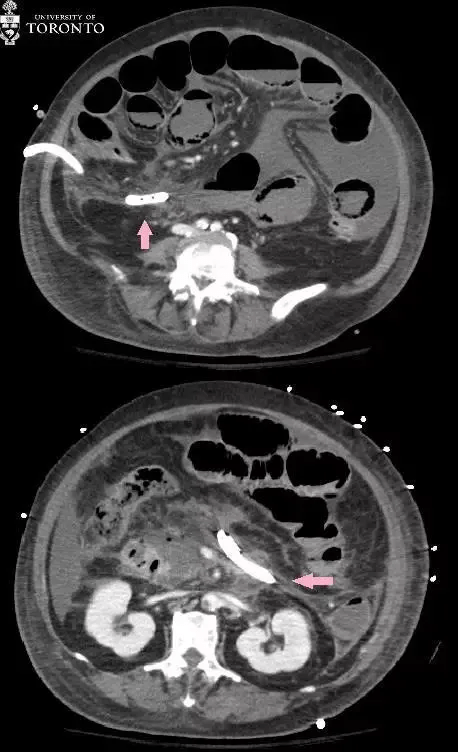

两处脓肿分别在超声引导(右)和 CT 引导(左)下行经皮穿刺引流术 。 16-Fr 多功能引流导管放置在脓肿中 , 吸出带碎屑的脓液 。 在随访的 CT 引导下引流中 , 排水管处于较好的位置(粉红色箭头) , 脓肿的大小也减少 , 但不幸的是 , 病人在出现肠系膜缺血不久后死亡 。